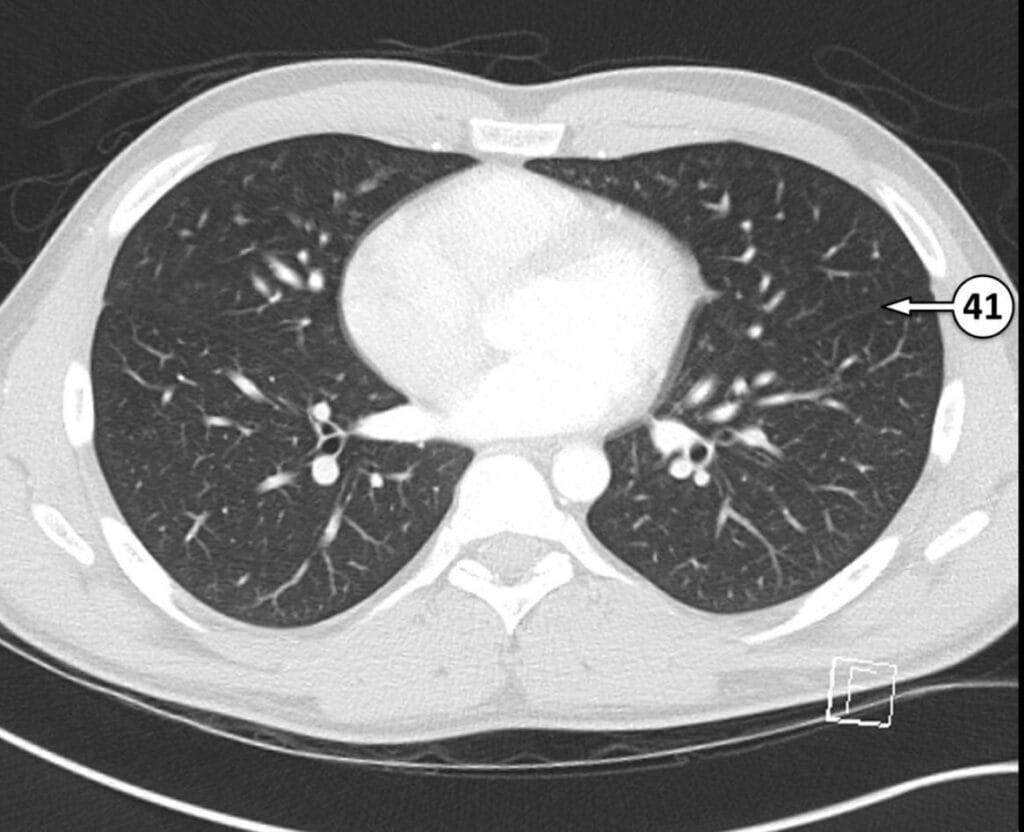

41. left oblique (major) fissure